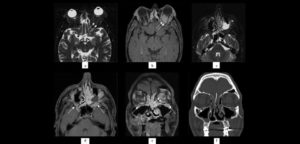

El pseudotumor inflamatorio (IPT) es una condición idiopática rara que puede ocurrir en casi todos los sitios del cuerpo, aunque más comúnmente implica el pulmón,